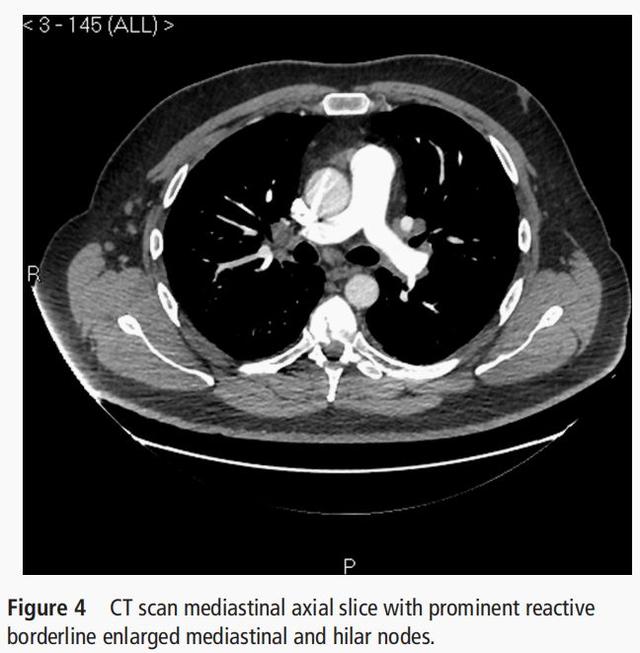

- 胸部CT显示双肺弥漫分布的马赛克 , 也不支持结节病 。

- 胸部CT显示双肺弥漫分布的马赛克 , 呼吸困难逐渐加重 , 肺功能示限制性通气功能障碍 , 弥散功能下降 , 目前考虑过敏性肺炎可能性最大 。